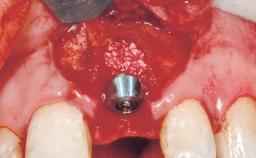

Late Flapless Placement of an Implant in a Maxillary Left Central Incisor Site

A 39-year-old male patient presented with a chief complaint of discomfort and gingival discoloration around his maxillary left central incisor. He was in good general health and was a non-smoker. His past dental history was significant because of the traumatic fracture of tooth 21 in a sporting accident at age 13. Initial dental treatment included endodontic therapy and a full-coverage restoration. The patient became symptomatic 5 years later, when structural failure of the tooth resulted in the dislodgment of the crown. Endodontic retreatment, apical surgery, and post-and-core restoration were performed.

| Bone Augmentation | Horizontal|Staged |

| Augmentation Materials | Xenogenous|Membrane |

| Soft Tissue Grafting | Simultaneous |